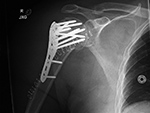

| Bilateral proximal humerus periarticular locking plates |

| 57 year-old man with comminuted bilateral proximal humerus fractures. Skin staples are present. There are old, healed rib fractures on the left. |